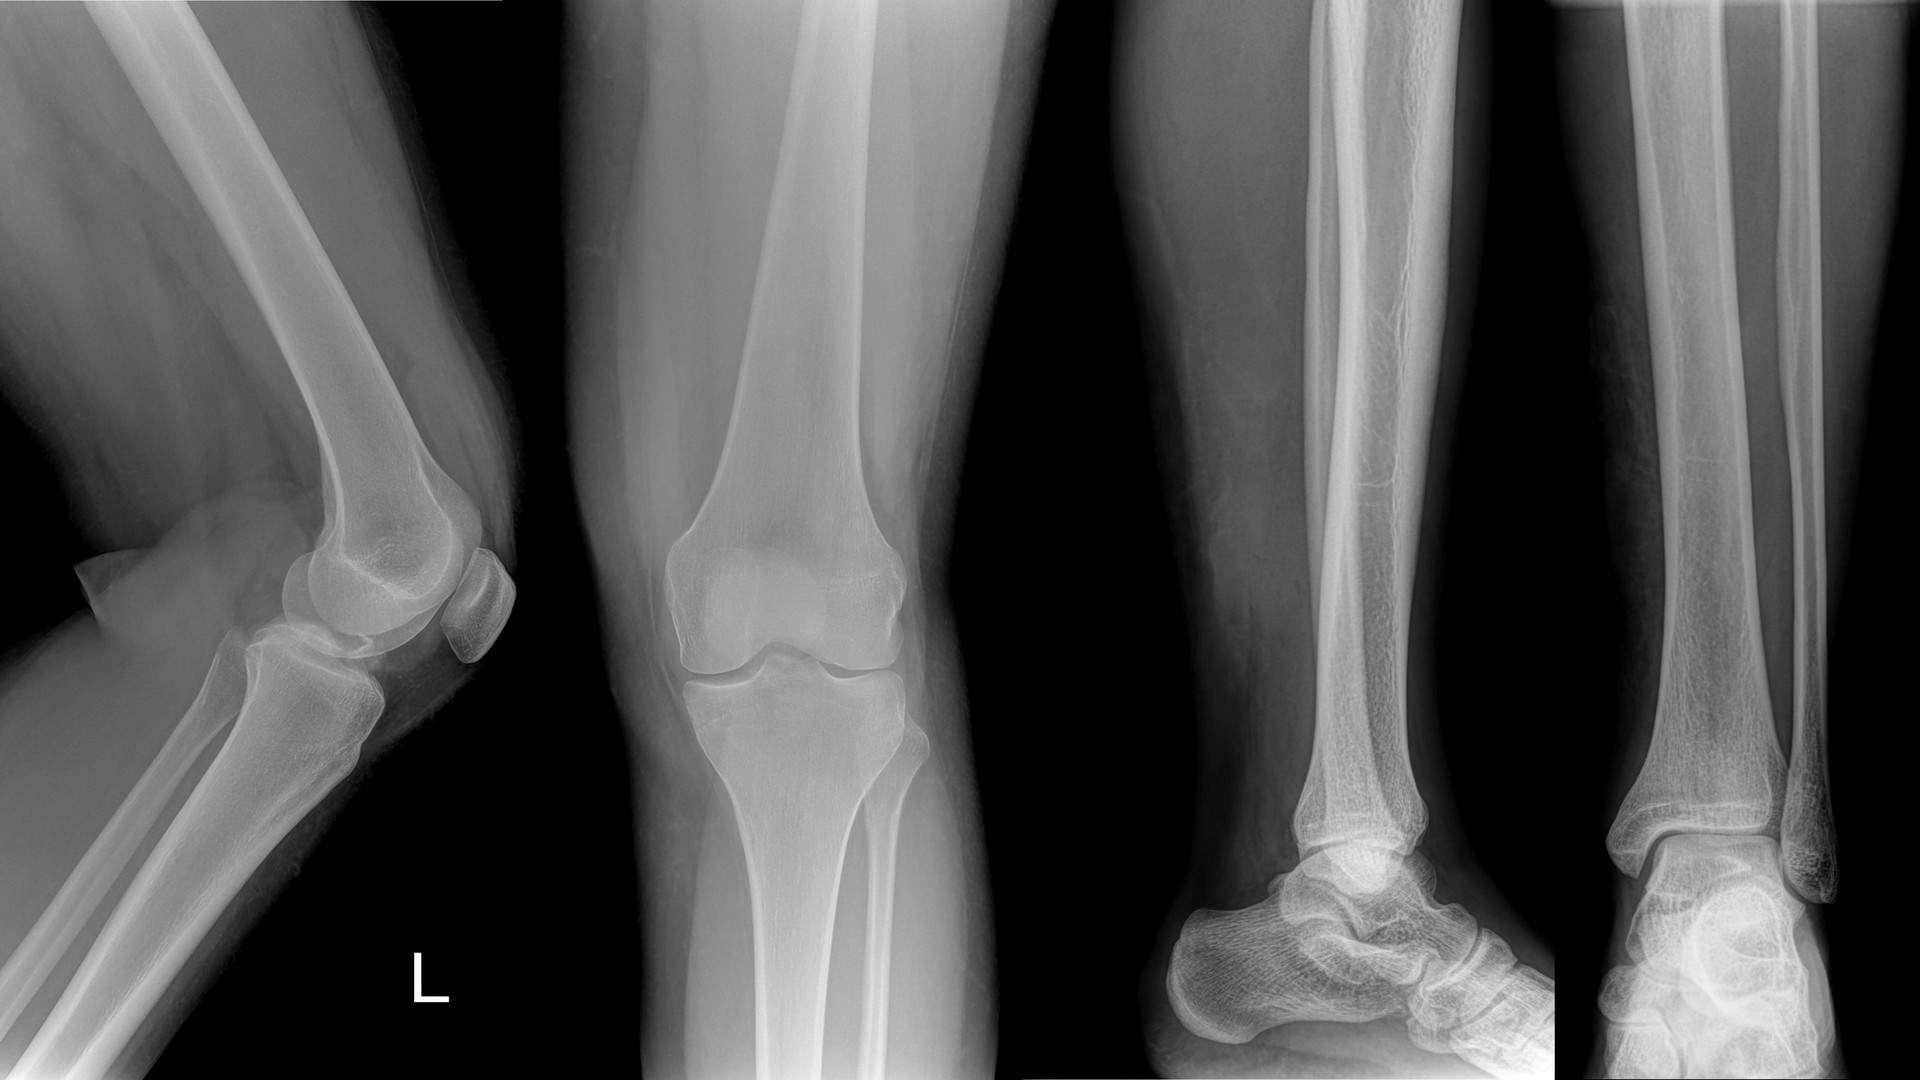

Gabinet urazowo-ortopedyczny, którego założycielem jest lekarz specjalista Jacek Piotr Osuch, znajduje się w Olkuszu i specjalizuje się w ortopedii oraz traumatologii narządu ruchu. Zapewniamy kompleksową obsługę pacjentów z chorobami zwyrodnieniowymi stawów, głównie biodrowych i kolanowych, a także z innymi schorzeniami oraz urazami układu kostno-stawowego i mięśniowo-ścięgnistego.

W naszym gabinecie zapewniamy wiele usług, począwszy od poradnictwa i diagnostyki w zakresie problemów kolan i bioder, przez leczenie zachowawcze, aż po leczenie operacyjne.